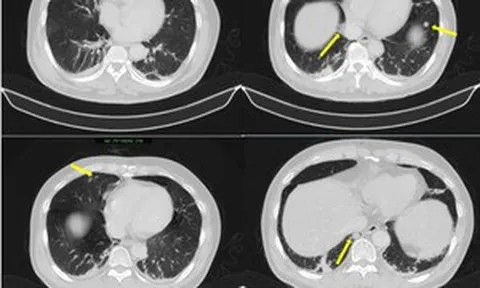

Trong quá trình phẫu thuật, khối u xơ có kích thước lớn, dính chặt vào nhiều cơ quan trong ổ bụng như phúc mạc, mạc nối lớn và quai ruột non. Đặc biệt, hệ thống mạch máu nuôi khối u tăng sinh mạnh, trong đó có những mạch máu đường kính lên đến 7 mm, cùng nhiều dải dính phức tạp, làm tăng đáng kể nguy cơ chảy máu và biến chứng trong mổ.

E-kip phẫu thuật đã lựa chọn đường mổ dọc để đảm bảo bộc lộ tối đa trường mổ, tạo điều kiện xử trí an toàn khối u kích thước lớn. Trong quá trình bóc tách khối u có hệ thống mạch máu tăng sinh phức tạp, các bác sĩ đã chủ động áp dụng kỹ thuật cầm máu bằng mũi may hình chữ nhật linh hoạt và hiệu quả.

Kỹ thuật này giúp kiểm soát tốt các điểm chảy máu lan tỏa trên diện rộng, đặc biệt tại vùng diện cắt và các vị trí mạch máu nuôi lớn, từ đó hạn chế tối đa mất máu trong mổ.

Kết thúc ca mổ, khối u đã được bóc tách hoàn toàn mà không gây tổn thương các tạng lân cận. Đặc biệt, tử cung của người bệnh được bảo tồn thành công, đây là yếu tố có ý nghĩa rất lớn đối với một bệnh nhân còn trẻ và chưa hoàn thành kế hoạch sinh sản.